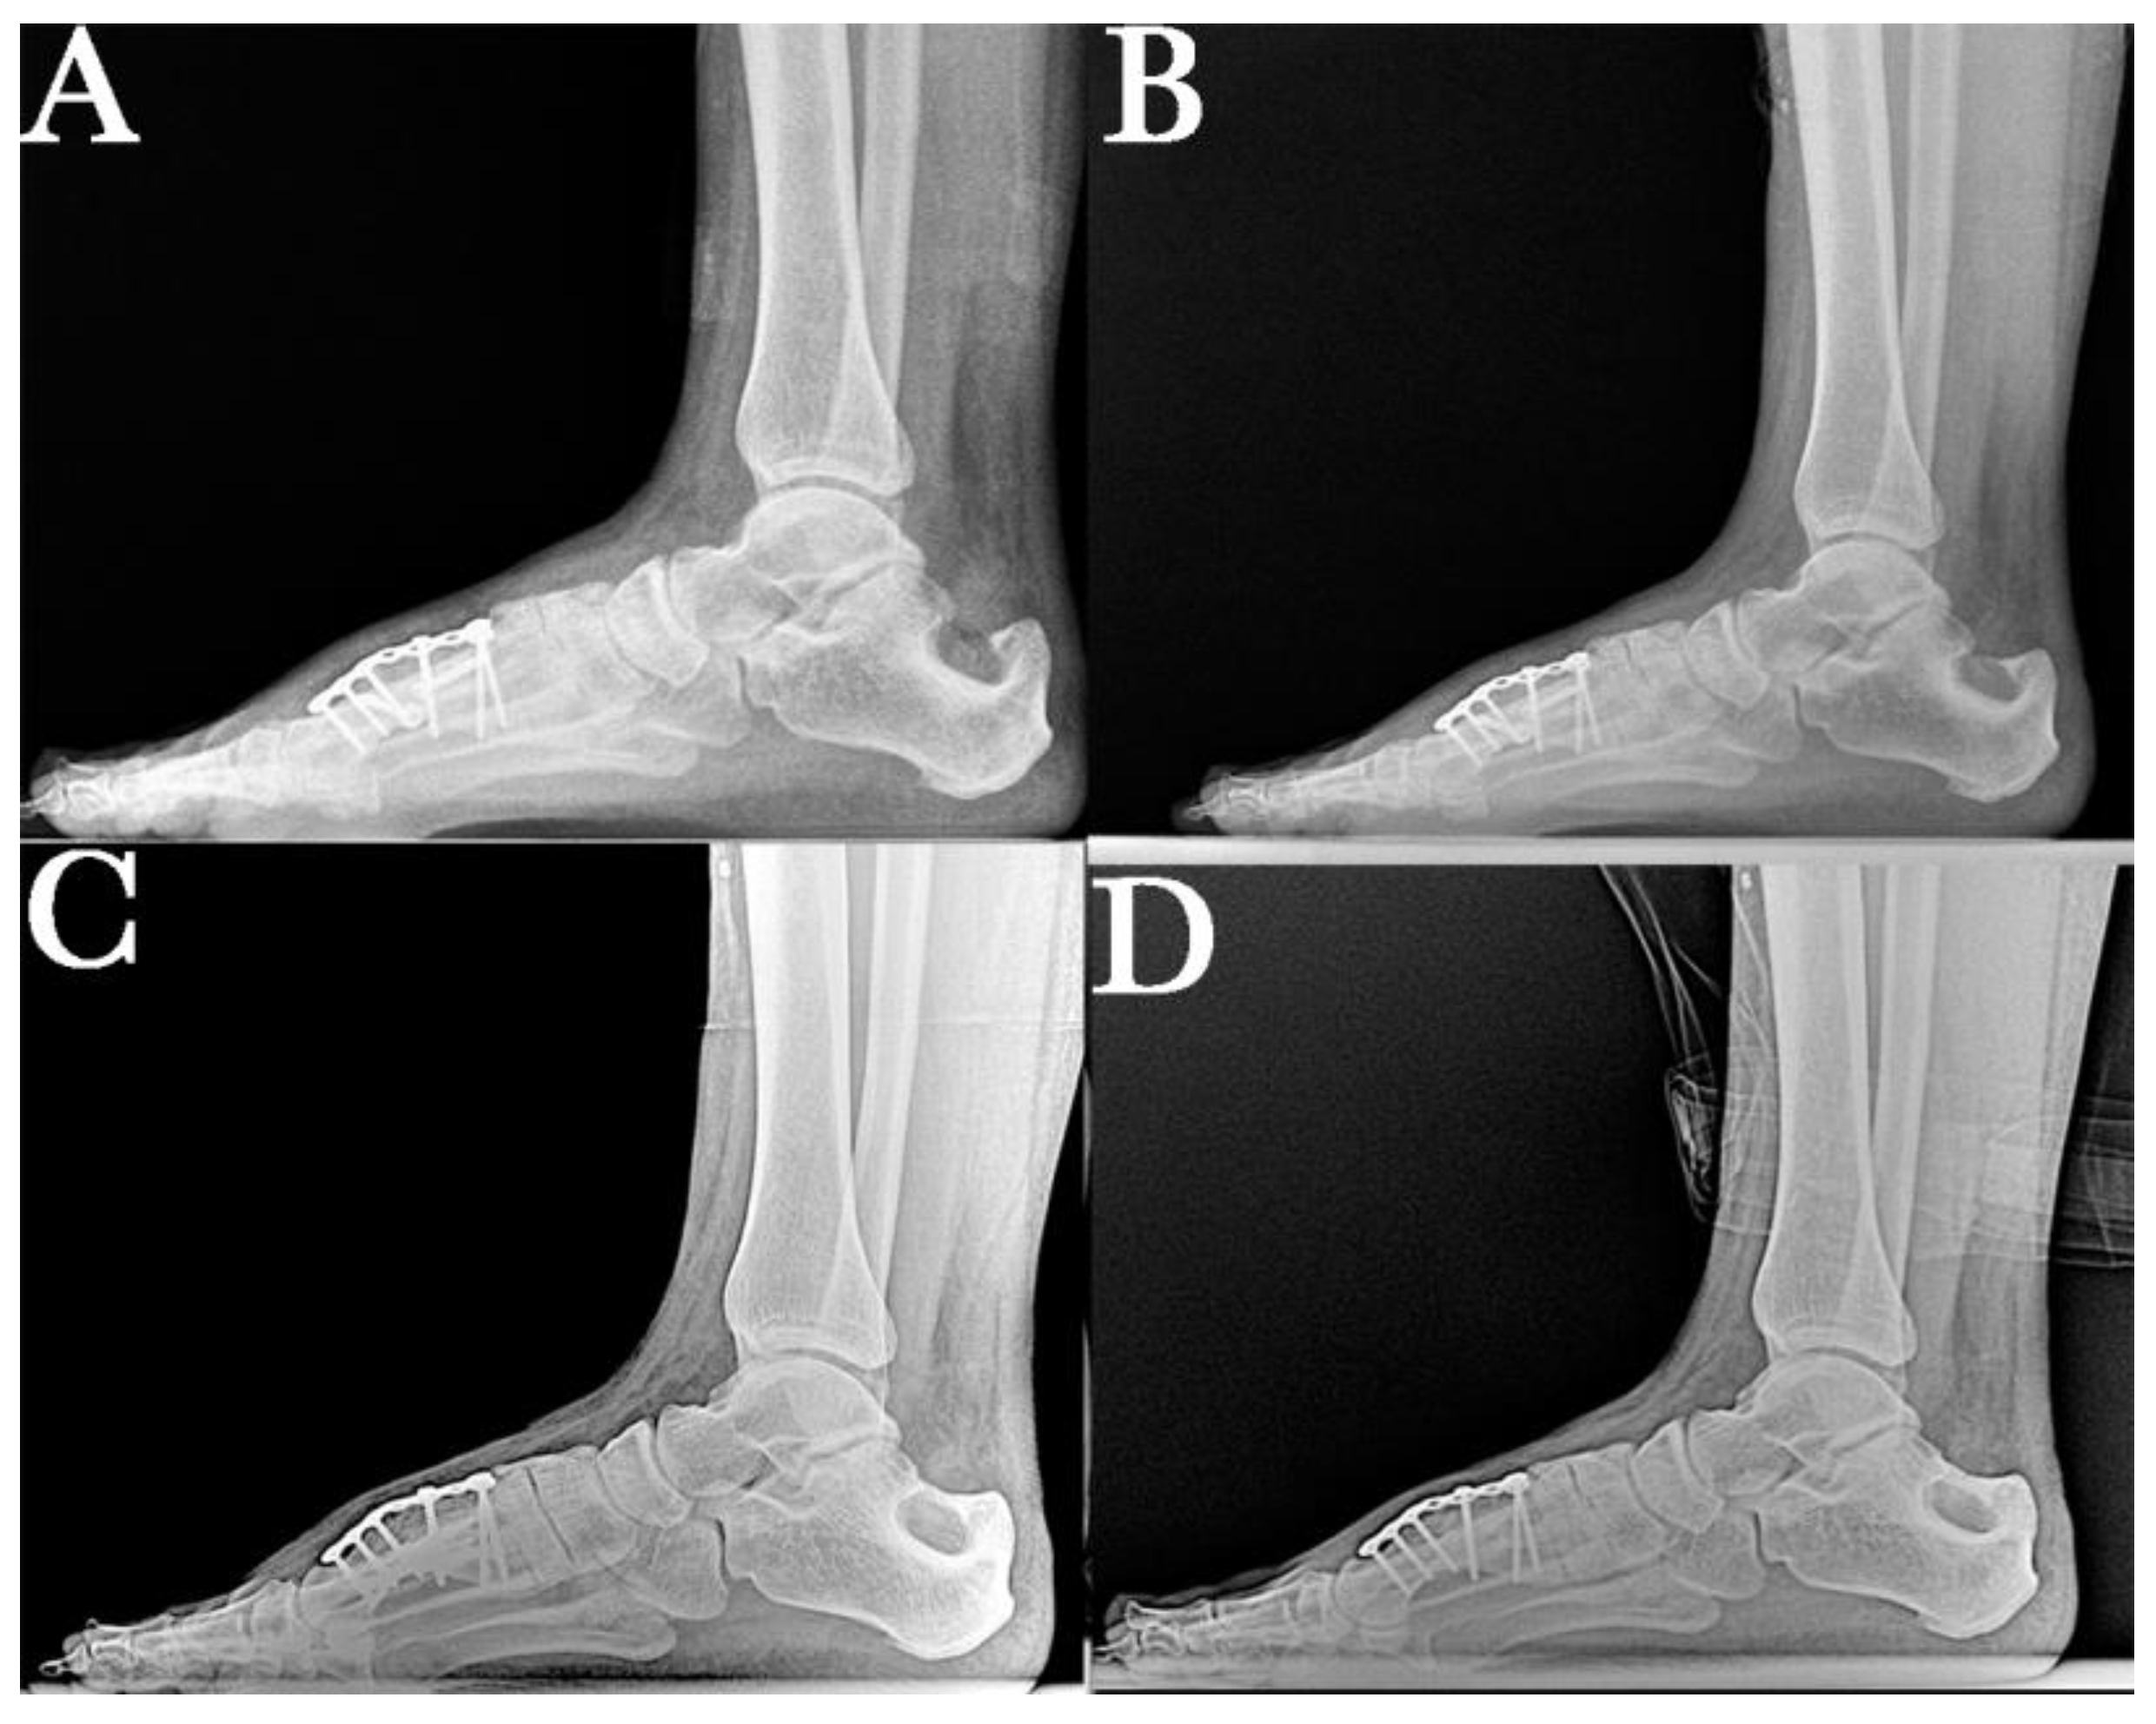

2. Case Report

2.1. Surgical Procedure

2.2. Postsurgical Procedure and Evolution

2.3. Results